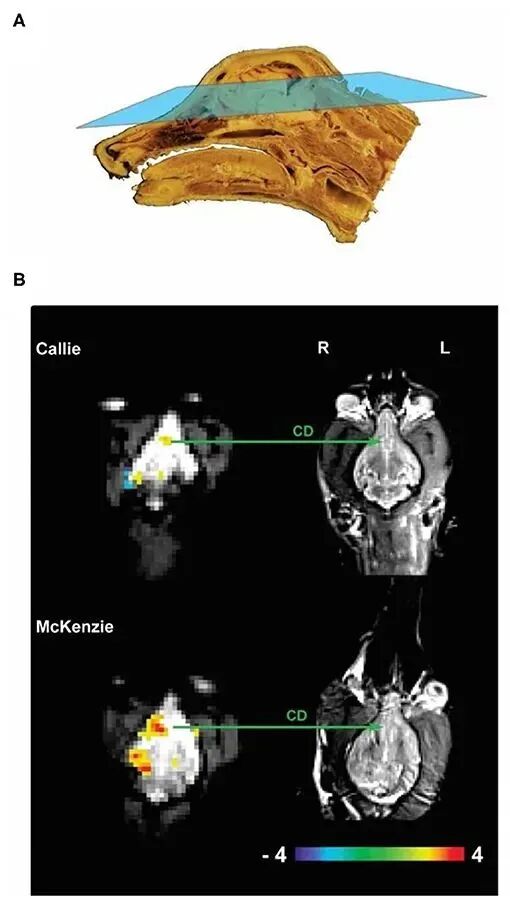

狗狗看到奖赏手势后大脑的变化|Berns, G. S., Brooks, A. M., and Spivak, M. 2012. Functional MRI in awake unrestrained dogs. PLoS ONE. 7:e38027. doi: 10.1371/journal.pone.0038027